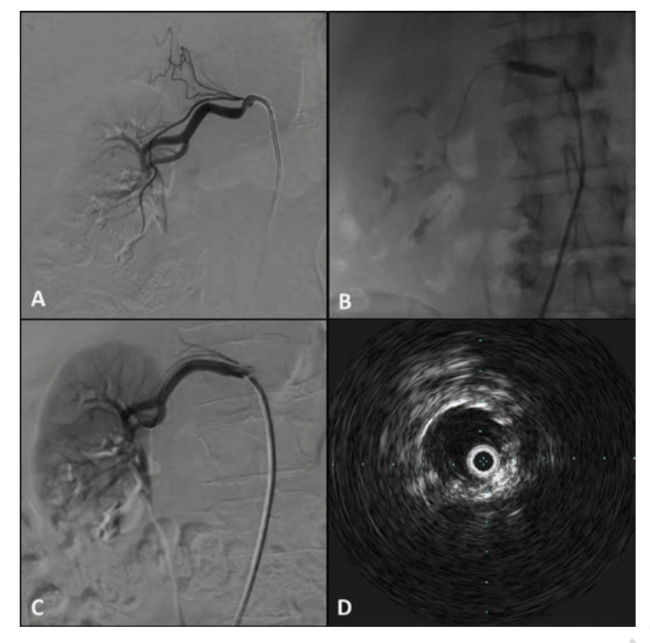

In August 2018, a 46-year-old man presented with refractory hypertension (203/93 mm Hg on admission) despite being on multiple antihypertensive medications including metoprolol, nifedipine, and hydrochlorothiazide with preserved renal function. His history was significant for tobacco abuse and recurrent admissions for chest pain, and his body mass index was 21 kg/m2. Angiography identified severe bilateral renal artery stenosis, with a proximal 95% focal stenosis of the ostial left renal artery (Figure 1A) and proximal 80% focal stenosis of the right renal artery (Figure 2A). Following a discussion of treatment options and risks, the patient consented to bilateral stenting of the renal arteries in the setting of refractory hypertension with multiple admissions and bilateral renal artery stenosis.

The guidewire was advanced up the femoral artery to the aorta, and through the ostium of the left renal artery to the proximal segment. Pre-dilation was achieved by loading a rapid-exchange 6.0 mm × 20 mm × 135 cm balloon catheter (Sterling Monorail, Boston Scientific) into the robot, advancing it to the obstruction, and inflating it at 4.0 atm. A rapid-exchange 5.0 mm × 19 mm × 150 cm pre-mounted, bare-metal stent system (Express SD, Boston Scientific) was loaded and deployed (Figure 1B). Intravascular ultrasound (IVUS) imaging of the stented segment was performed to confirm adequate size of the vessel for optimization. Post dilation with the Sterling 6.0 mm x 20 mm balloon resulted in mild underexpansion of the stent, so a 7.0 mm × 20 mm balloon (Advance 18LP, Cook Medical) was used to achieve complete expansion. Final angiogram of the left renal artery confirmed adequate stent expansion and apposition with brisk flow (Figure 1C). Repeat IVUS imaging confirmed adequate stent expansion and apposition (Figure 1D). The procedure was repeated for the right renal artery (Figure 2B-D) with robotic-assisted wiring, pre-dilation, stenting, intravascular imaging, and post dilation. Final angiogram of the right renal artery confirmed adequate stent expansion and apposition with brisk flow.